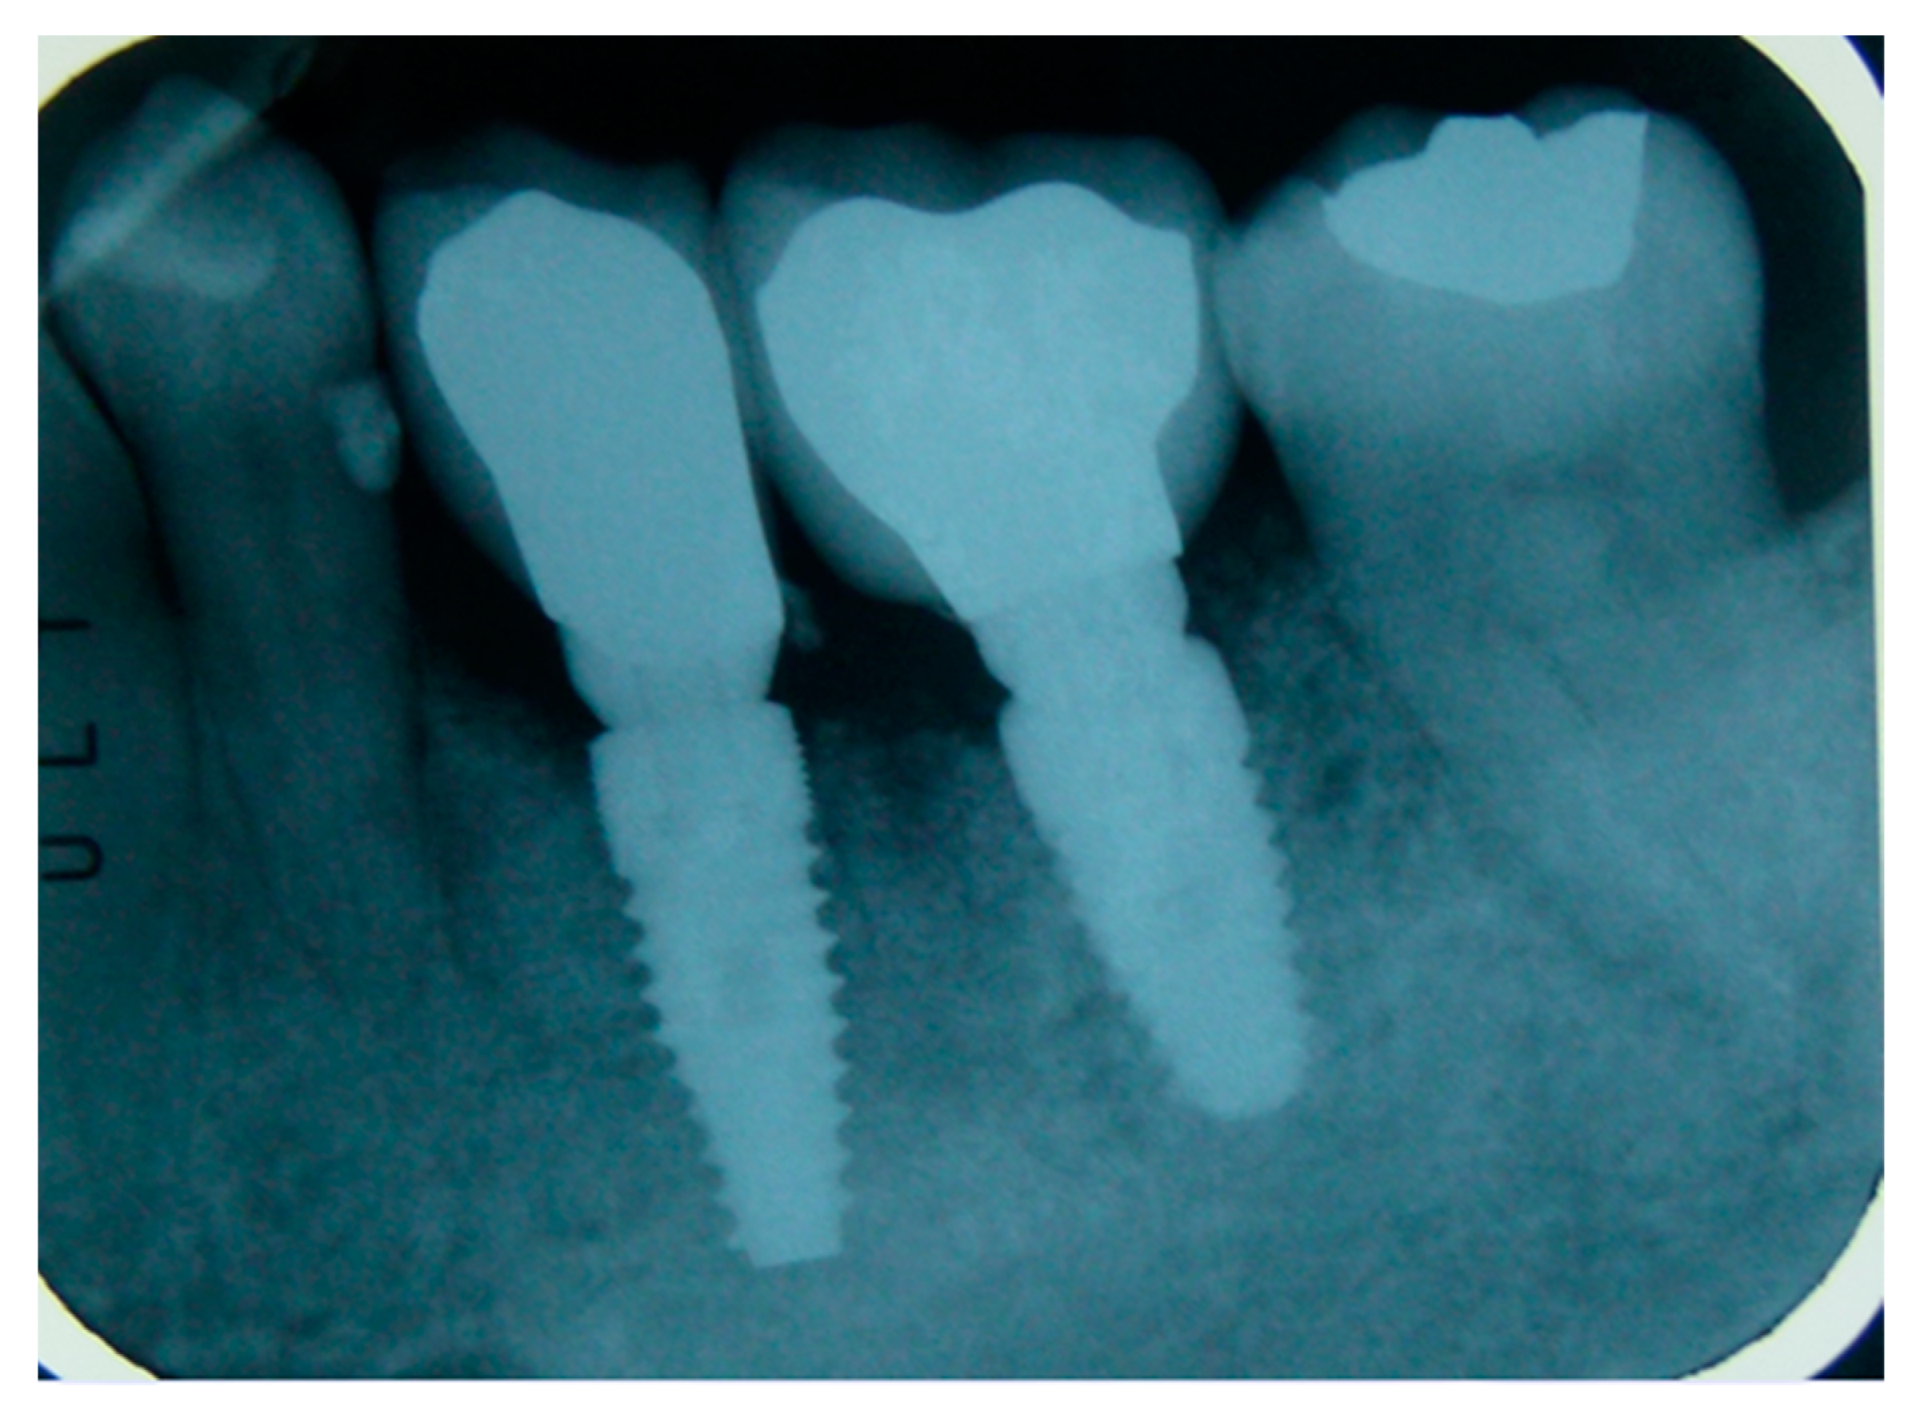

| Implants | 106 (Certain—3i Biomet) |

| 3,25–4–5 mm diameter | |

| 10–11,5–13 mm lenght | |

| Implant failure | 1 |